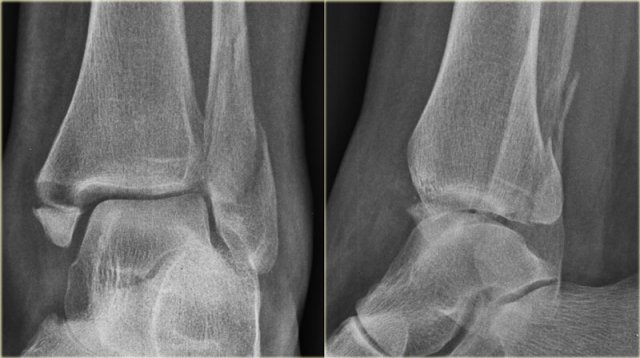

Weber C fracture - stage 3 Weber C fracture - stage 3

The radiographs shows a Weber C fracture.

There is an avulsion fracture of the medial malleolus and a fibula fracture above the level of the syndesmosis.

According to Lauge-Hansen this is stage 3 pronation exorotation injury and so the anterior syndesmosis (stage 2) must also be ruptured.

We do not see a tertius fracture, which would indicate stage 4, but there may be a rupture of the posterior syndesmosis.